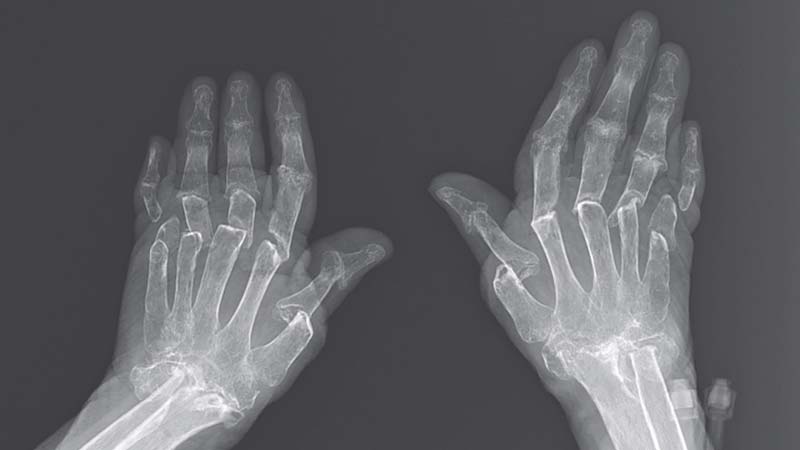

En yaygın romatizmal hastalıklardan olan artrit ise eklemlerin iltihaplanmasına verilen isimdir. Acı, sertleşme, sıcaklık ve kızarıp morarmak artritin yaygın belirtilerindendir. Artrit bir eklemde veya bir kaç eklemde medyana gelebilir. Artrite yakalanmanın bir çok sebebi vardır. Romatizmal hastaların yanı sıra birçok başka hastalıklar da artrite yol açabilir. Romatizmal hastalıklar, darbe alma, enfeksiyon kapma ve kötü huylu hastalıklar da artrite yol açabilir. Sebeplerinden yola çıkarak artrit türlerinin tedavisinin de farklı olduğu söylenebilir.

Kireçlenmek için ağrının özellikleri diğer romatizmal hastalıklara göre farklıdır. Çünkü tam tersi dinlenme ile iyileşir, hareketlenme ile şiddetlenir. Sabahleyin eklemlerde duyulan kuruluk hissi ise daha kısa süreli olup genelde yarım saatten daha az bir süre sürer. Çoğu romatizmal hastalıkların ortak özelliklerinden biri de eklemlerde ödemin görülmesi ve eklemlerin manevra alanı ve gücünün azalmasıdır. Eklemlerin yüzeyinin morarması da kimi romatizmal hastalık türlerinde görülür.

Romatizmal hastalıkları olan kişilere ilk aşamalarda müdahale edilmezse eklemlerin sürekli bir şekilde zarar görmesi muhtemeldir. Çoğu romatizmal hastalar eklemlerinden başka, diğer organlarda da sorunlar yaşayabilirler. Örneğin artrit romatoit hastalığında, cilt,gözler ve akciğer, Lupus hastalığında tüm organlar, Behçet sendromunda ağız, cinsel organlar, cilt, gözler, sinirsel sistem ve terleme düzeni de etkilenebilir. Ayrıca sklerodermi hastalığında da cilt, sindirim sistemi, akciğer ve böbrek, Poimiyozit hastalığında ise kaslar, akciğer, Vaskülit hastalığında tüm organlar, reaksiyonel artritte, göz, cilt ve cinsel organlar, Psoriatik Artrit'te ise cilt, gözler, Sjögren sendromunda ise sümük ve balgam etkilenir.